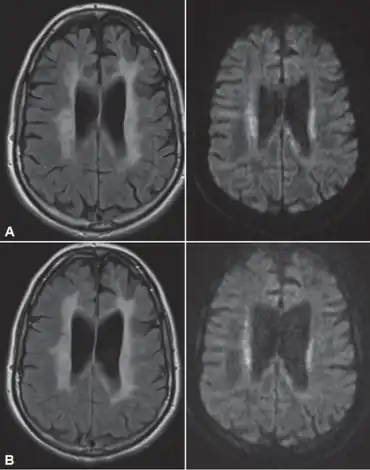

In HDLS, there is enlargement of the lateral ventricles and marked thinning or weakening of cerebral white matter.[6] The loss of white matter is caused by myelin loss. These changes are associated with diffuse gliosis, moderate loss of axons and many axonal spheroids.[1]

Neuroimaging

Standard MRI scans have been performed on 1.5 Tesla scanners with 5 mm thickness and 5 mm spacing to screen for white matter lesions in identified families. If signal intensities of the MRI scans are higher in white matter regions than in grey matter regions, the patient is considered to be at risk for HDLS, although a number of other disorders can also produce white matter changes and the findings are not diagnostic without genetic testing or pathologic confirmation.[2]